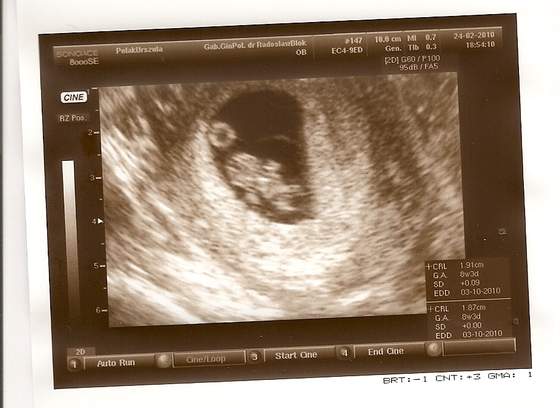

Jak to mój mąż wuefista stwierdził: widać już łapki i piłkę do ręcznej... :-)

Już ma prawie 2 cm... :tak:

Niesamowite, jak przez dwa tygodnie te nasze dzidzie się zmieniają. :-D